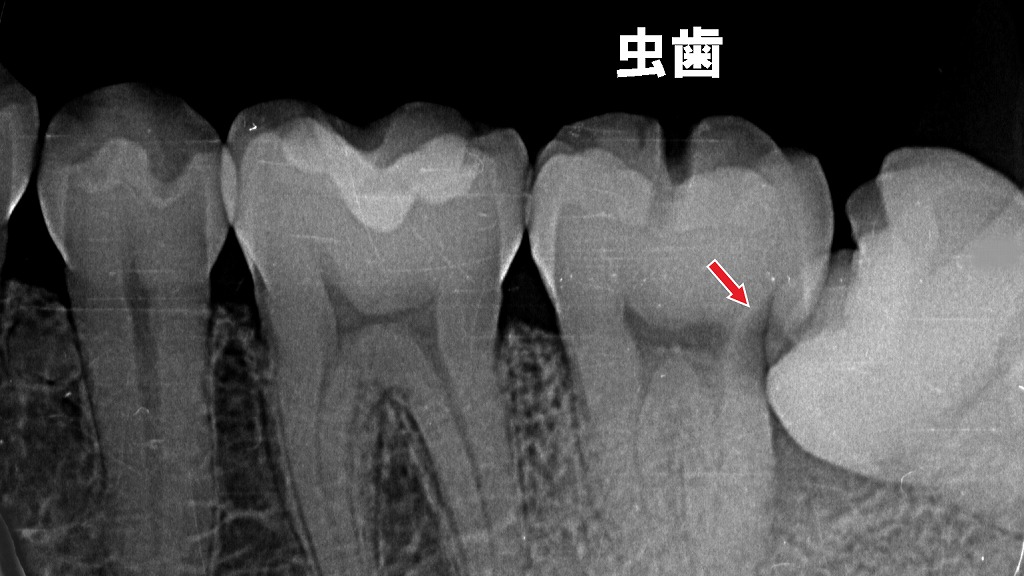

噛むと歯が痛くなる原因のひとつが、親知らずの“圧迫”です。

画像のように、横向きの親知らずが前の歯を強く押すように生えてくると、その部分に虫歯や歯の揺れ・圧痛が起きやすくなります。

この圧迫によって、噛んだ時だけ痛む・違和感が続くといった症状につながります。